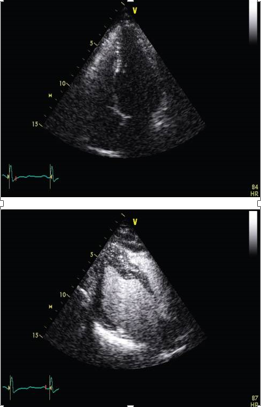

Contrast Echocardiography

Contrast echocardiography has various clinical implications, particularly in the evaluation of intracardiac shunts. [45] Initially, agitated saline injection through a peripheral vein was utilized for this purpose. However, the inability to control the intensity of the contrast effect posed a significant challenge. To overcome this limitation, stable contrast agents were developed, specifically designed to opacify the right-sided cardiac chambers and assess intracardiac shunts. [46] This advancement resolved the problem of uncontrolled contrast intensity.

Subsequent studies demonstrated that intravenous left heart contrast agents not only enhance the definition of the left ventricular endocardial border but also improve image quality in patients with suboptimal image views (see [Figure 3]). [46], [47] In cases of ischemic heart disease, intravenous contrast agents can be employed to investigate myocardial perfusion. These agents offer valuable insights into the blood flow patterns within the myocardium.